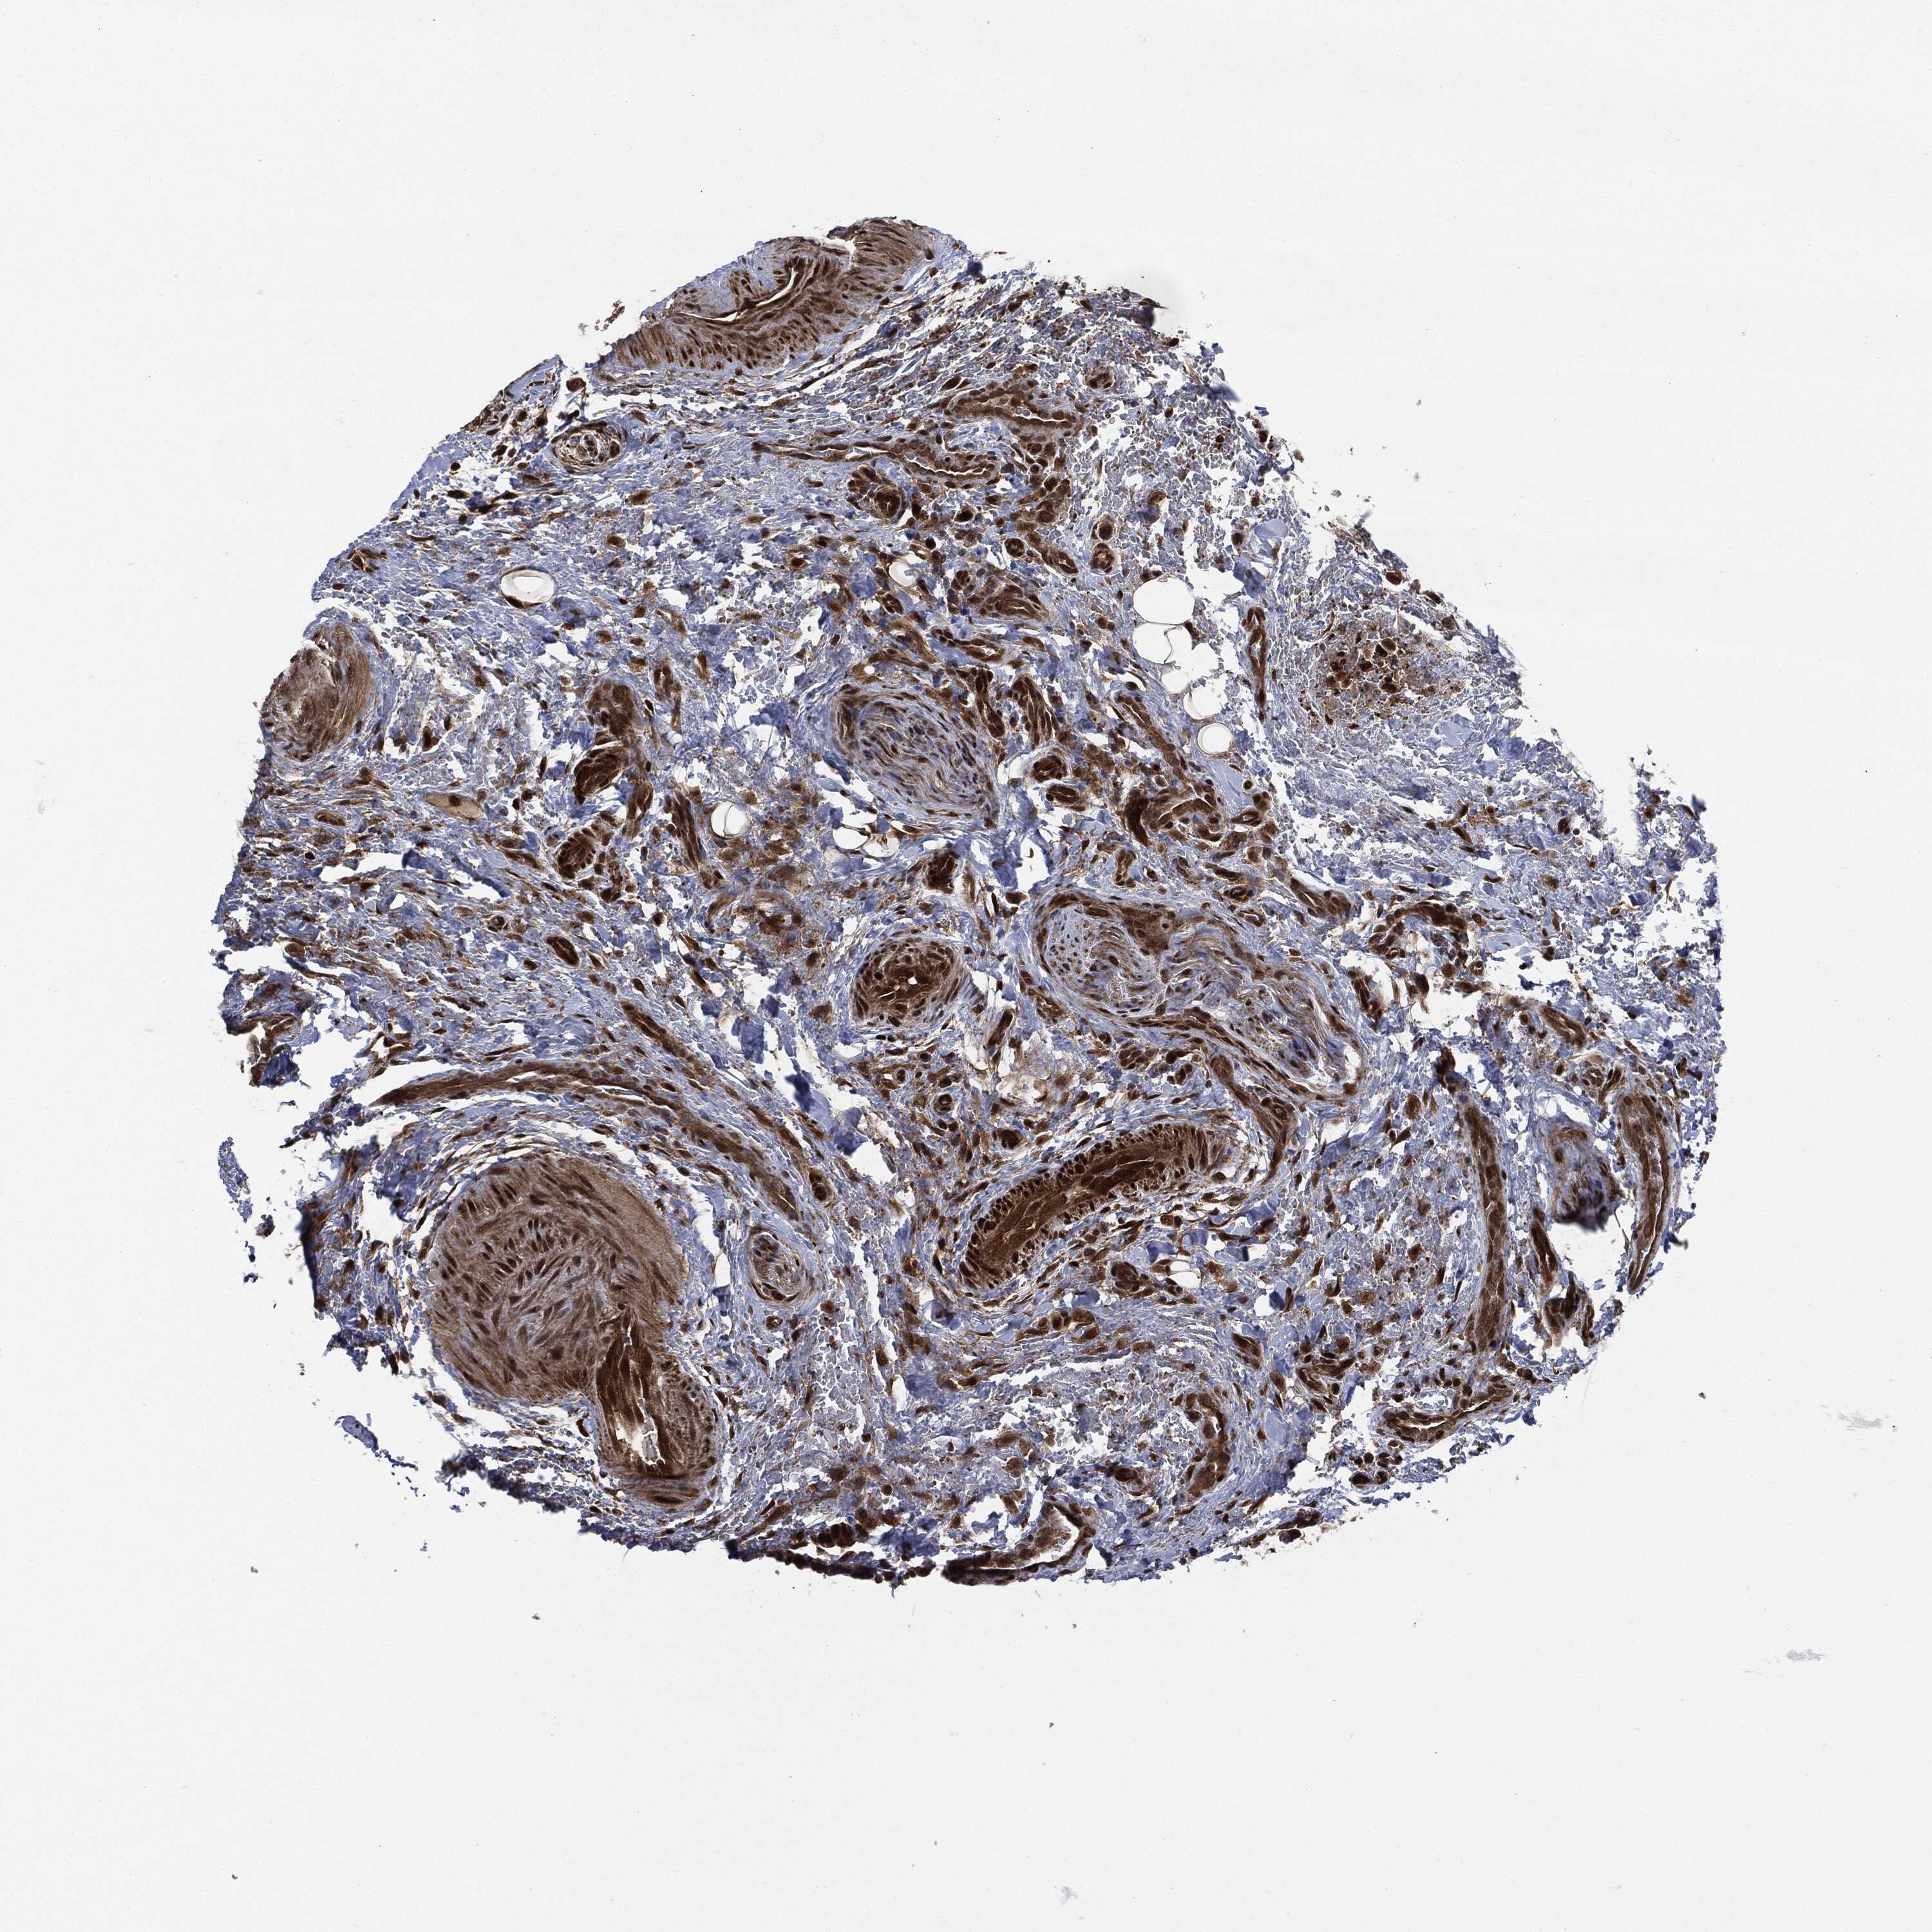

THYROID CANCER - Protein expressioni

A mouse-over function shows sample information and annotation data. Click on an image to view it in a full screen mode. Samples can be filtered based on level of antibody staining by selecting one or several of the following categories: high, medium, low and not detected. The assay and annotation is described here.

Note that samples used for immunohistochemistry by the Human Protein Atlas do not correspond to samples in the TCGA dataset.

Antibody stainingi

Antibody staining in the annotated cell types in the current human tissue is reported as not detected, low, medium, or high, based on conventional immunohistochemistry profiling in selected tissues. This score is based on the combination of the staining intensity and fraction of stained cells.

Each image is clickable and will lead to virtual microscopy that enables deeper exploration of all samples and also displays staining intensity scores, fraction scores and subcellular localization as well as patient and tissue information for each sample.

Antibody HPA034635

Antibody HPA069977

Antibody HPA071875

Antibody CAB009108

Staining

High

Medium

Low

Not detected

Intensity

Strong

Moderate

Weak

Negative

Quantity

>75%

75%-25%

<25%

None

Location

Nuclear

Cytoplasmic/membranous

Cytoplasmic/membranous,nuclear

Papillary adenocarcinoma, NOS

Follicular adenoma carcinoma, NOS